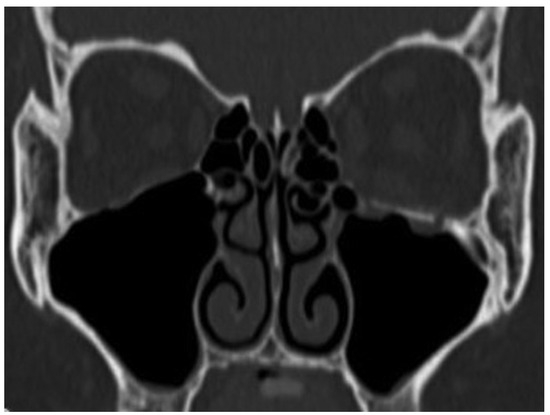

Tarsorrhaphy was done and kept for 1 day to prevent the swelling of conjunctiva, and the exercise of eye movements started soon. Coronal CT after surgery revealed good position of the bone graft to orbital floor at 4 weeks after surgery (Figure 5). The diplopia was rectified completely in 7 weeks after surgery (Figure 6).

Figure 5. Coronal view of CT after surgery.